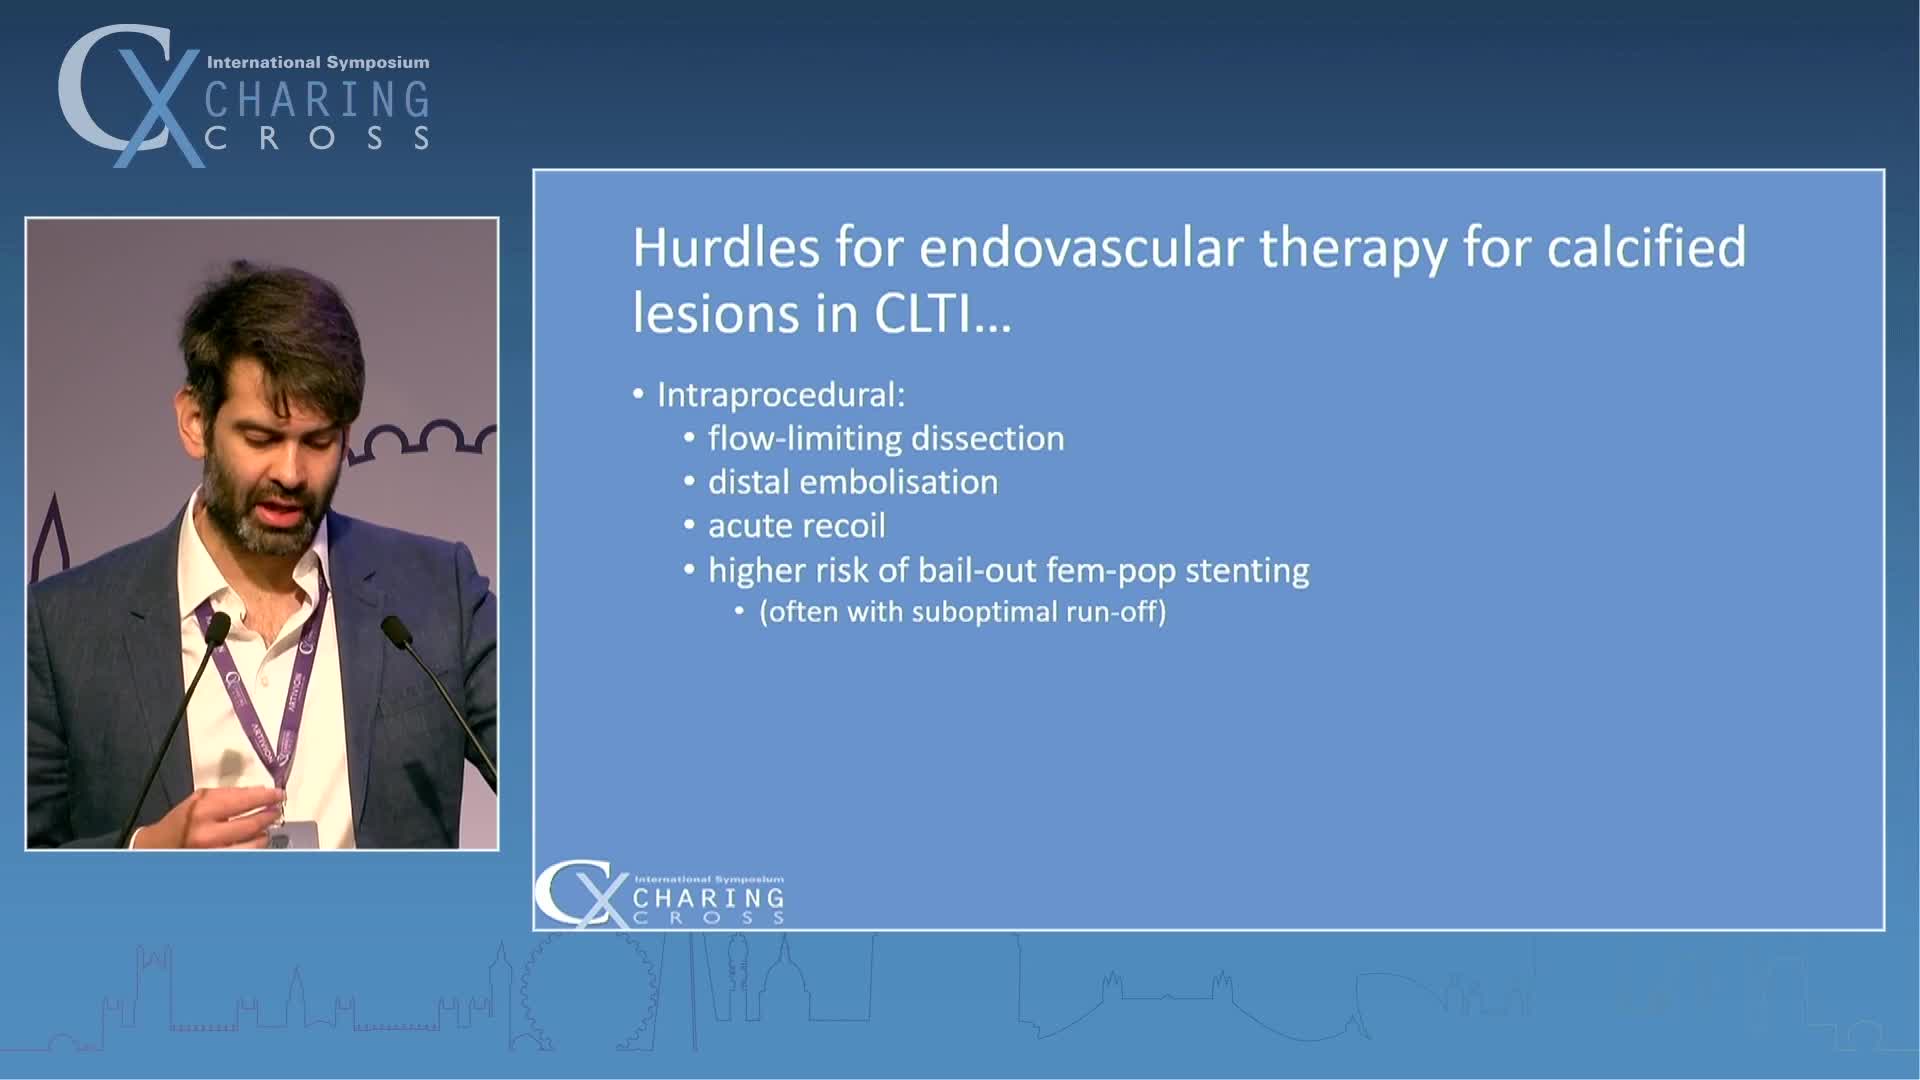

IVL cracking the calcium conundrum in PAD

Simplify your procedures with Intravascular Lithotripsy (IVL) by safely modifying intimal and medial calcium to achieve optimal outcomes while minimising trauma, complications and costs due to its unique MOA.